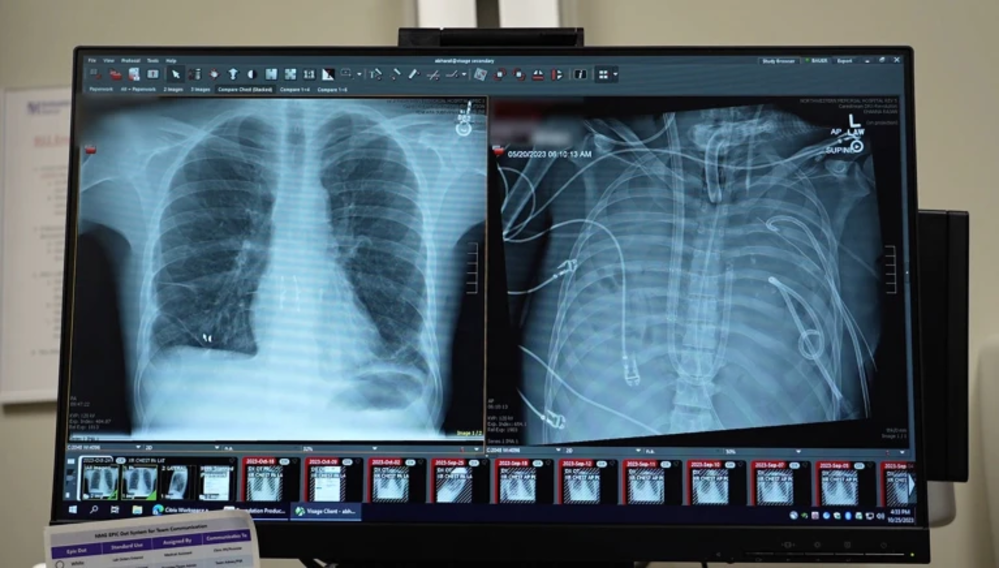

Мужчина прожил 48 часов без легких благодаря искусственной системе

33-летний пациент пережил 48 часов без собственных легких благодаря новой системе искусственного дыхания, разработанной командой из Медицинской школы Файнберга Северо-Западного университета в Чикаго. Аппарат поддерживал жизнь до того, как мужчине сделали двойную пересадку легких.

Ранее люди подключались к внешним устройствам, которые насыщают кровь кислородом, но такие системы не считались полноценными искусственными легкими. Они не обеспечивали нормальную работу сердца, так как кровь не циркулировала через него. По словам Анкита Бхарата, торакального хирурга и одного из разработчиков, их система уникальна именно потому, что поддерживает сбалансированный кровоток к сердцу, снижая риск тромбов и инфаркта. Результаты работы опубликованы в журнале Med.

Поскольку пересадка легких сразу была невозможна, хирурги удалили инфицированные органы и подключили пациента к системе искусственных легких.

Система была изначально разработана для больных COVID-19 с тяжелыми повреждениями легких, чтобы поддерживать их состояние до возможности пересадки. Она представляет собой модифицированную версию экстракорпоральной мембранной оксигенации (ЭКМО). Ключевое отличие — аппарат подключен к сердцу, обеспечивая правильное давление для циркуляции крови и полноценную работу сердца, в отличие от классической ЭКМО, где легкие остаются в теле пациента.